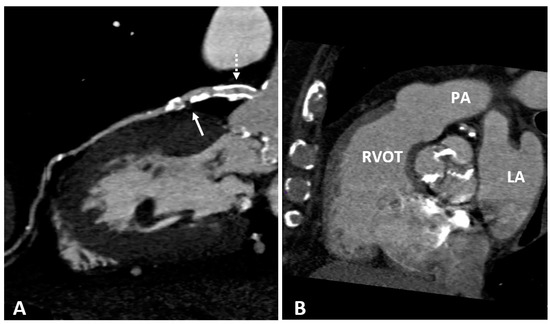

Coronary angiography is the anatomic reference standard for coronary imaging. Providing direct visualization of the degree of luminal narrowing with excellent spatial and temporal resolution, it is the imaging modality of choice for symptomatic, high-risk patients (Figure 4). Compared to intravascular ultrasound or optical coherence tomography, coronary angiography has low sensitivity. While large calcified plaques are well visualized, the sensitivity for smaller lesions is limited, due to low spatial resolution (about 1 mm) [100]. Although angiography is optimal for outlining contrast-filled coronary lumen, it cannot provide information on structures that are below the endothelium. The atherosclerotic burden, especially in the earlier stage of disease when positive coronary remodeling may allow apparently normal lumen size despite the presence of wall plaques, is underestimated. Also, the degree of anatomic stenosis is only modestly correlated with hemodynamic functional significance [101]. Since most acute coronary syndromes are not consequences of occlusion at the site of severe stenosis but result from rupture of small plaques associated with only mild to moderate stenosis, angiography is limited in predicting CV events [2,102].

Figure 4.

Selective angiography of the left coronary artery. (A) Normal coronary anatomy: left main, left anterior descending (LAD), left circumflex, and their branches are patent. (B) Focal severe narrowing of the lumen (arrow) due to a 90% stenosis in the proximal segment of the LAD.